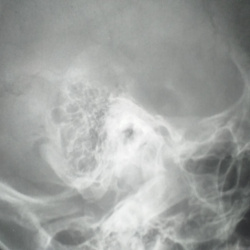

Женщина 45 лет. Как бы Вы описали ППН и как бы заключились?. Вижу в правой в/ч пазухе две доп тени.

16.04.2024 - 20:46